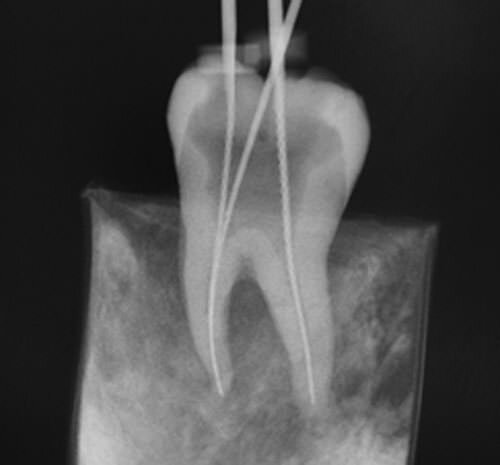

• RX PARA CONDUCTOMETRÍA

RX PARA CONDUCTOMETRÍA

C. Edmund Kells fue el primero en utilizar los rayos X para verificar si el conducto radicular había sido bien obturado.